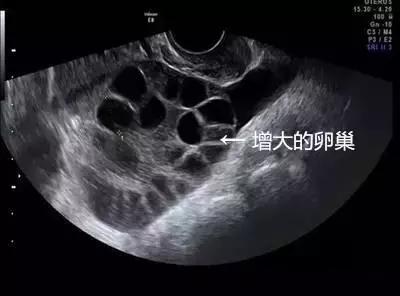

取卵成功后,中介就没有再联系琳琳。但取卵5天后,琳琳出现持续性下腹胀,还有十分明显的胸闷症状。她再次联系卖卵中介,但对方拒绝承担责任,还威胁琳琳不要再纠缠。琳琳到这家妇幼保健院就诊,B超提示腹腔内大量积液,胸腔少量积液,卵巢增大超过3倍以上,考虑是卵巢过度刺激综合症,被收治住院。

由于腹腔内积液增多,肚子大了一圈,琳琳无法平躺,入眠困难,进食困难,非常痛苦。在先后进行2次腹腔穿刺抽出腹水后,症状才得以缓解,最后住院10天左右才得以出院。